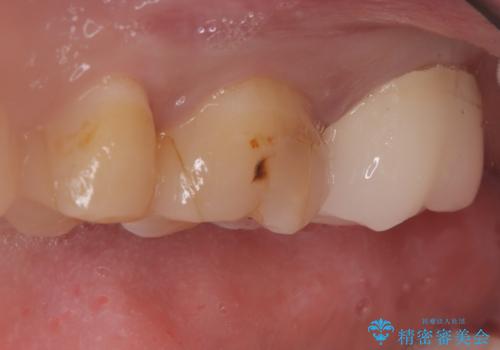

【セラミッククラウン】インレーの下の大きな虫歯

- レントゲンにて昔入れたインレーの下に虫歯が見つかった患者様です。

歯髄に近接する虫歯でしたが、根管治療は必要なくクラウンにて修復を行うことができました。